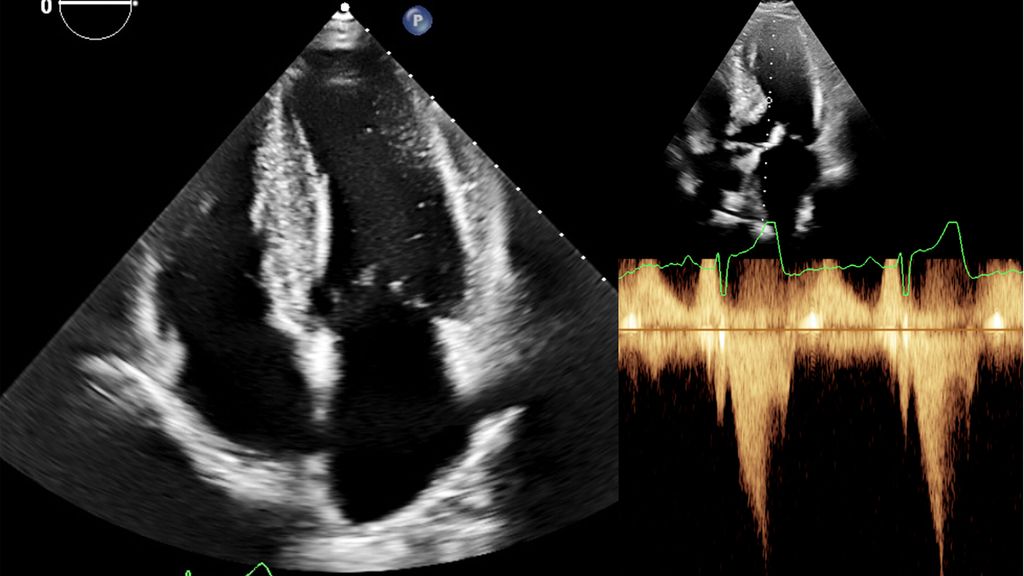

Dennoch ist die Echokardiografie aufgrund der niederschwelligen Verfügbarkeit als erste Untersuchungsmodalität und zur Verlaufsbeurteilung nicht wegzudenken. Mit der Ejektionsfraktion, der Vorhofgröße und der Beurteilung der diastolischen Funktion können prognostisch wichtige Parameter erhoben werden. Ein „apical sparing“ in der Analyse des myokardialen Strains oder der Aspekt eines „granular sparkling“ kann einen Verdacht auf kardiale Amyloidose begründen (Abb.3). Jede echokardiografische Untersuchung wegen des Verdachts auf LVH sollte außerdem eine Bestimmung des LVOT-Gradienten inkl. Valsalva-Manöver beinhalten (Abb.2).